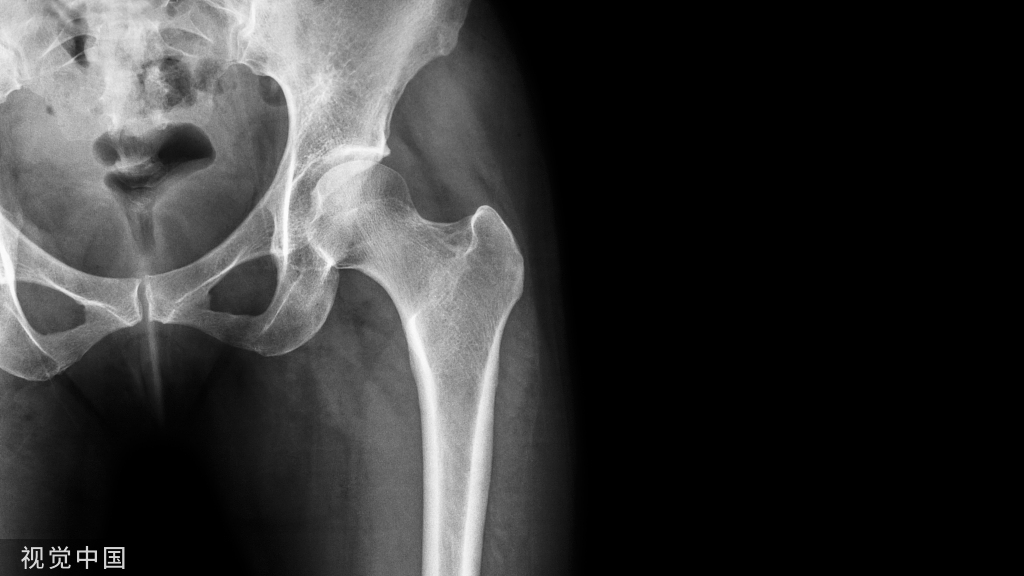

病例6 一例82岁髋部外伤患者,非移位股骨颈骨折,在CT横断面可见积脂血症,MR证实股骨颈骨折。关节积脂血症在非移位股骨颈骨折的识别中作用明显。